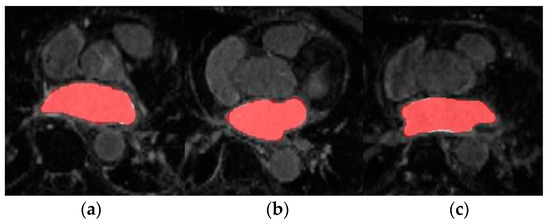

4.2. Source Domain Model

Firstly, the dual 3D U-Net was trained and tested with a large number of labelled images from LGE-MRI (source) domain. For this, Database 1 was employed which contains 100 volumes each of them composed of 88 slices. The aim of this experiment was to pre-train the network and obtain a high-performance model from which knowledge can be inferred. The mean Dice coefficient and standard deviation obtained during evaluation across the 20 testing volumes were 0.9155 ± 0.0270. The segmentation results for three representative patients and slices of Database 1 can be observed in Figure 4.

In this section, we review the results obtained in the different experiments presented in Section 4. Firstly, the source network was trained with a large number of annotated LGE-MRI samples (Database 1). As can be observed, the model achieved very high accuracy segmentation results. This is expected as Database 1 corresponds to the data provided by the 2018 LA segmentation challenge [25], and the network proposed by [14] was specifically designed to face this challenge. Therefore, by keeping the same learning parameters, the Dice obtained coincides with the Dice reported in [14] (0.91–0.92). The segmentation masks shown in Figure 5 further highlight the high-accuracy performance of this model.

Figure 4. Axial slices of LA segmentations for three representative patients (ac) obtained through the LGE-MRI source model. Ground-truth mask in white, prediction mask in red and intersection in pink.